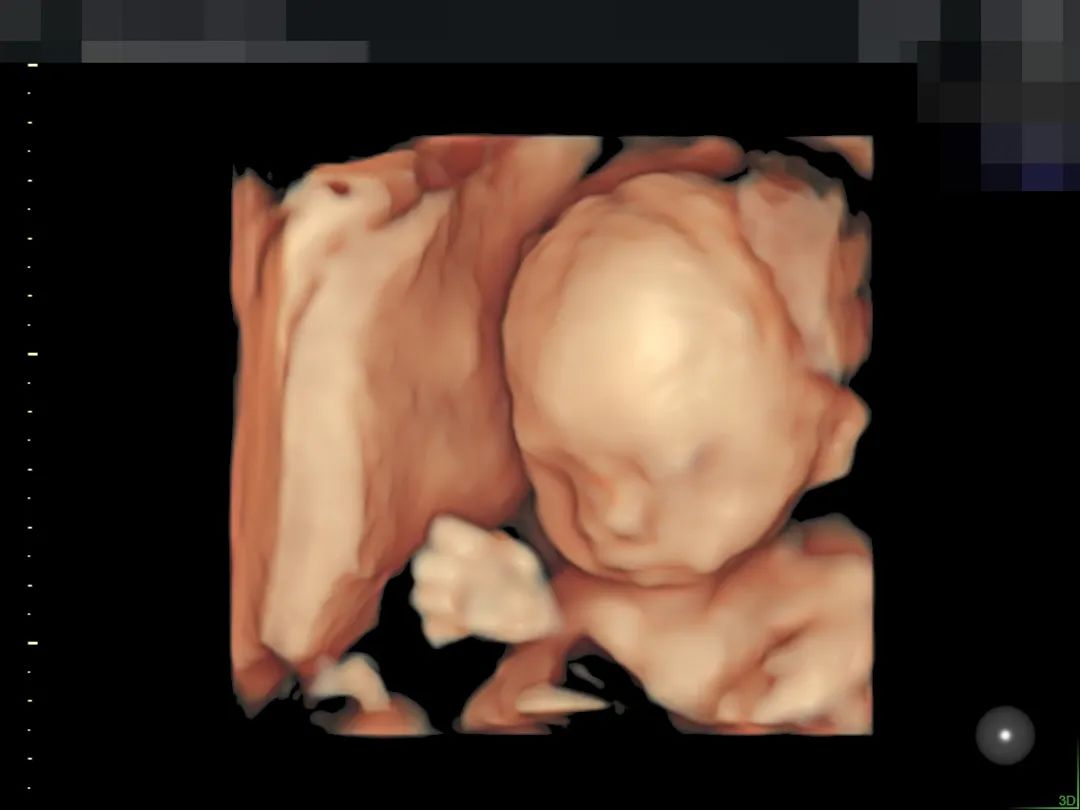

▲190斤孕妈王女士,不仅做了全面筛查,还留下了宝贵的胎儿影像,全家人都非常满意

▲孕妈肚皮脂肪较厚,羊水情况也不好,在和平进行了全面筛查